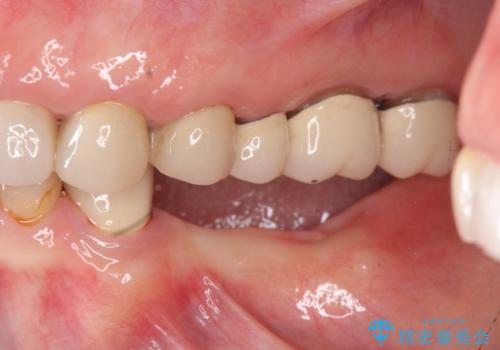

- 80万円(インプラント×2・アバットメント×2・ジルコニアクラウン×3)費用は治療当時の料金となります

そのような場合、歯牙欠損状態の放置もしくはインプラント治療の選択になりますが残っている歯への負担も大きいためインプラント治療による咬合機能回復を推奨しております。